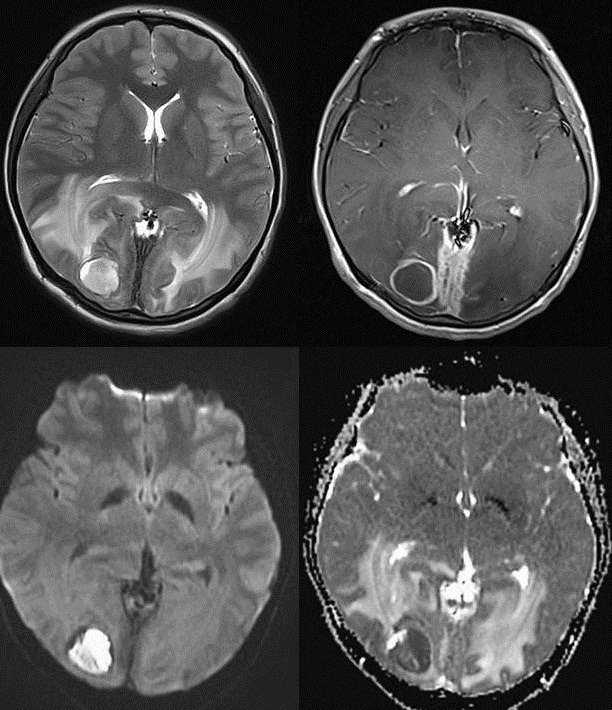

After contrast administration there is a ring or a homogeneous disk like enhancementwithin the region. First lets take a look at the importance of using contrast in detecting lesions the mri on the left is pre. Ct or mri with lesions having an enhancing ring of contrast around a less dense center can indicate certain neurological infections injuries and indolent disorders.

A ring enhancing lesion is an abnormal radiologic sign on mri or ct scans obtained using radiocontraston the image there is an area of decreased density see radiodensity surrounded by a bright rim from concentration of the enhancing contrast dyethis enhancement may represent breakdown of the blood brain barrier and the development of an inflammatory capsule.